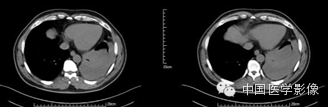

病例1【病史】

患者男,50岁。

患者因“突发胸痛4余天”入院。患者无发热、盗汗,无声音嘶哑,无咳痰,无面部及双下肢肿胀。门诊以“左前上纵膈肿瘤”收入院。患者自发病以来,饮食睡眠可,大小便正常,体重较前无明显减轻。既往高血压病史1年,否认其他传染病史。

专科查体:胸廓对称,双侧呼吸动度均等,胸壁无明显压痛及肿块,双侧语颤正常,双肺叩清音,左下肺呼吸音低,右肺呼吸音可,双肺未闻及干湿啰音。

入院诊断:左前上纵膈肿瘤:畸胎瘤?

【影像资料】

平扫

动脉期

静脉期

延迟期

【病理结果】

孤立性纤维性肿瘤